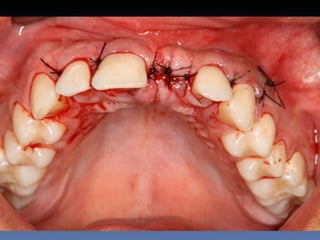

BOX 5

Maria Gomes Moraes

Idade – 53 anos

Sexo – Feminino

Raça – Caucasiana

ASA – II

Data- 23-04-2012

Diagnóstico: Atrofia severa

da pré-maxila.

Plano de tratamento: Aumento de volume horizontal

com blocos ósseos autógenos “onlay” provenientes do

Ramus da Mandíbula.

sutura nylon 4-0

Pós-operatório -5 dias